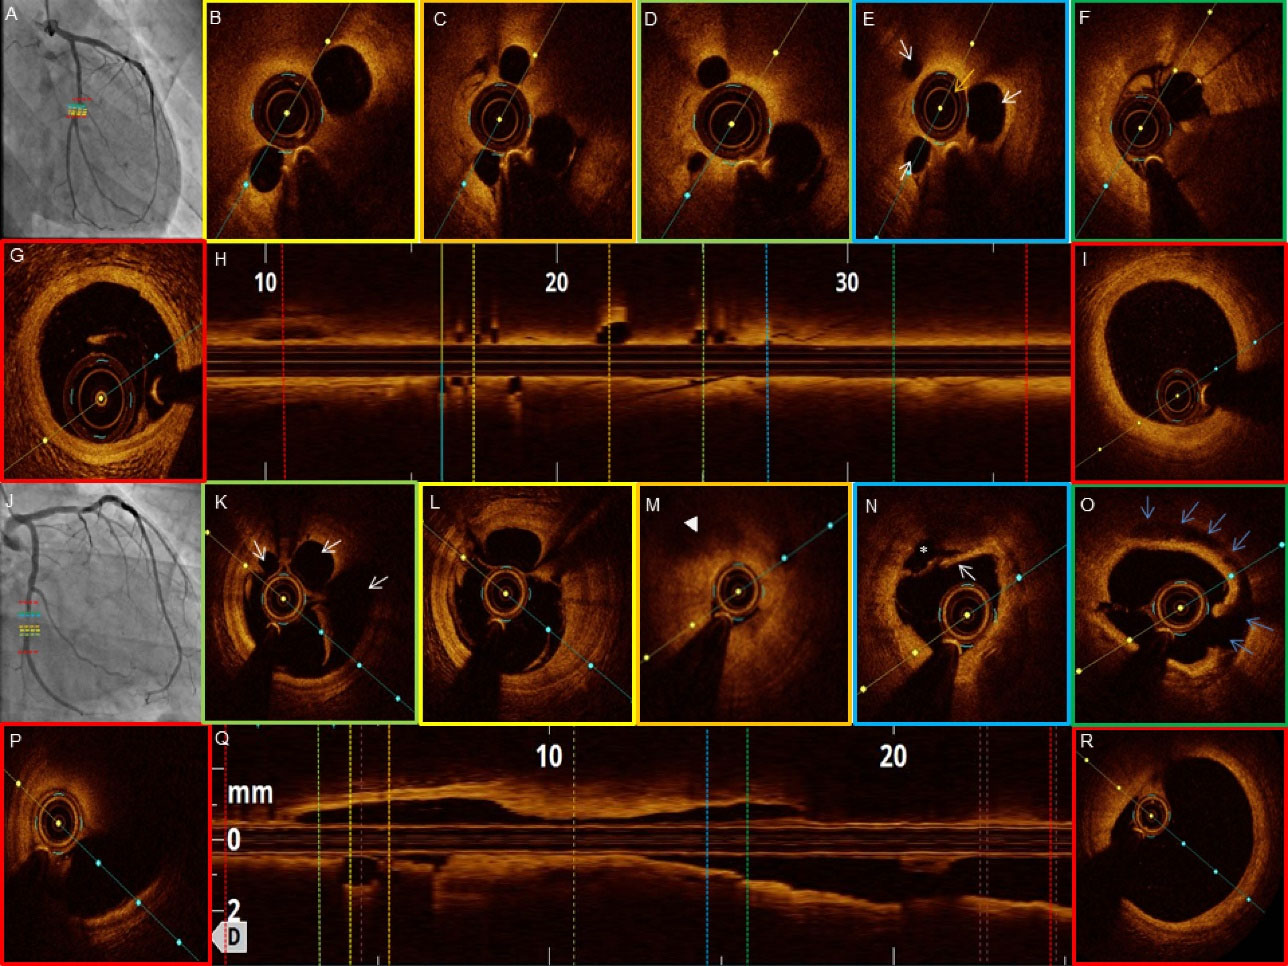

jcvtr-14-220-g003

Figure 3. OCT images of patient #3-4 (LAD) with veiled appearance and pseudo-dissection respectively (A and J).

jcvtr-14-220-g004

Figure 4. OCT images of patient #5-6 (LAD). Braided like appearance on angiogram (A and J). (D) multiple small cavities with thin septae (white arrows) giving ‘swiss cheese’ appearance. (L and N) small cavities with thin septa (‘lotus root’ or ‘swiss cheese’ appearance).